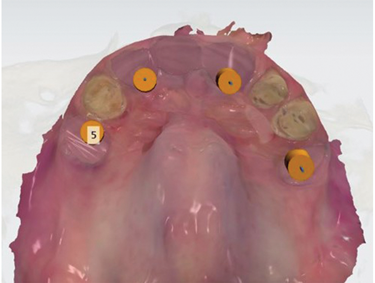

The laboratory virtually extracted teeth Nos. 6, 10, and 11 and designed the provisional restoration, copying the original bridge design (Figure 9 and Figure 10). The die spacer thickness parameter was set to cement gap 0.045 mm with an extra cement gap of 0.065 mm. This file was then imported into surgical planning and guide design software, and final implant positions were planned for the area where implants could be placed (Figure 11 through Figure 13). This plan was verified by the clinicians, and the surgical guide was designed to sit on the prepared teeth (Figure 14).

Fig 13. The teeth to be clinically extracted were now virtually extracted, leaving only the abutment teeth.

Fig 14. The surgical guide was designed to be supported by the three remaining teeth.